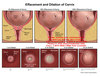

Define Preterm Labor

regular uterine ctx that ➜ cervical diLation < 37 WG